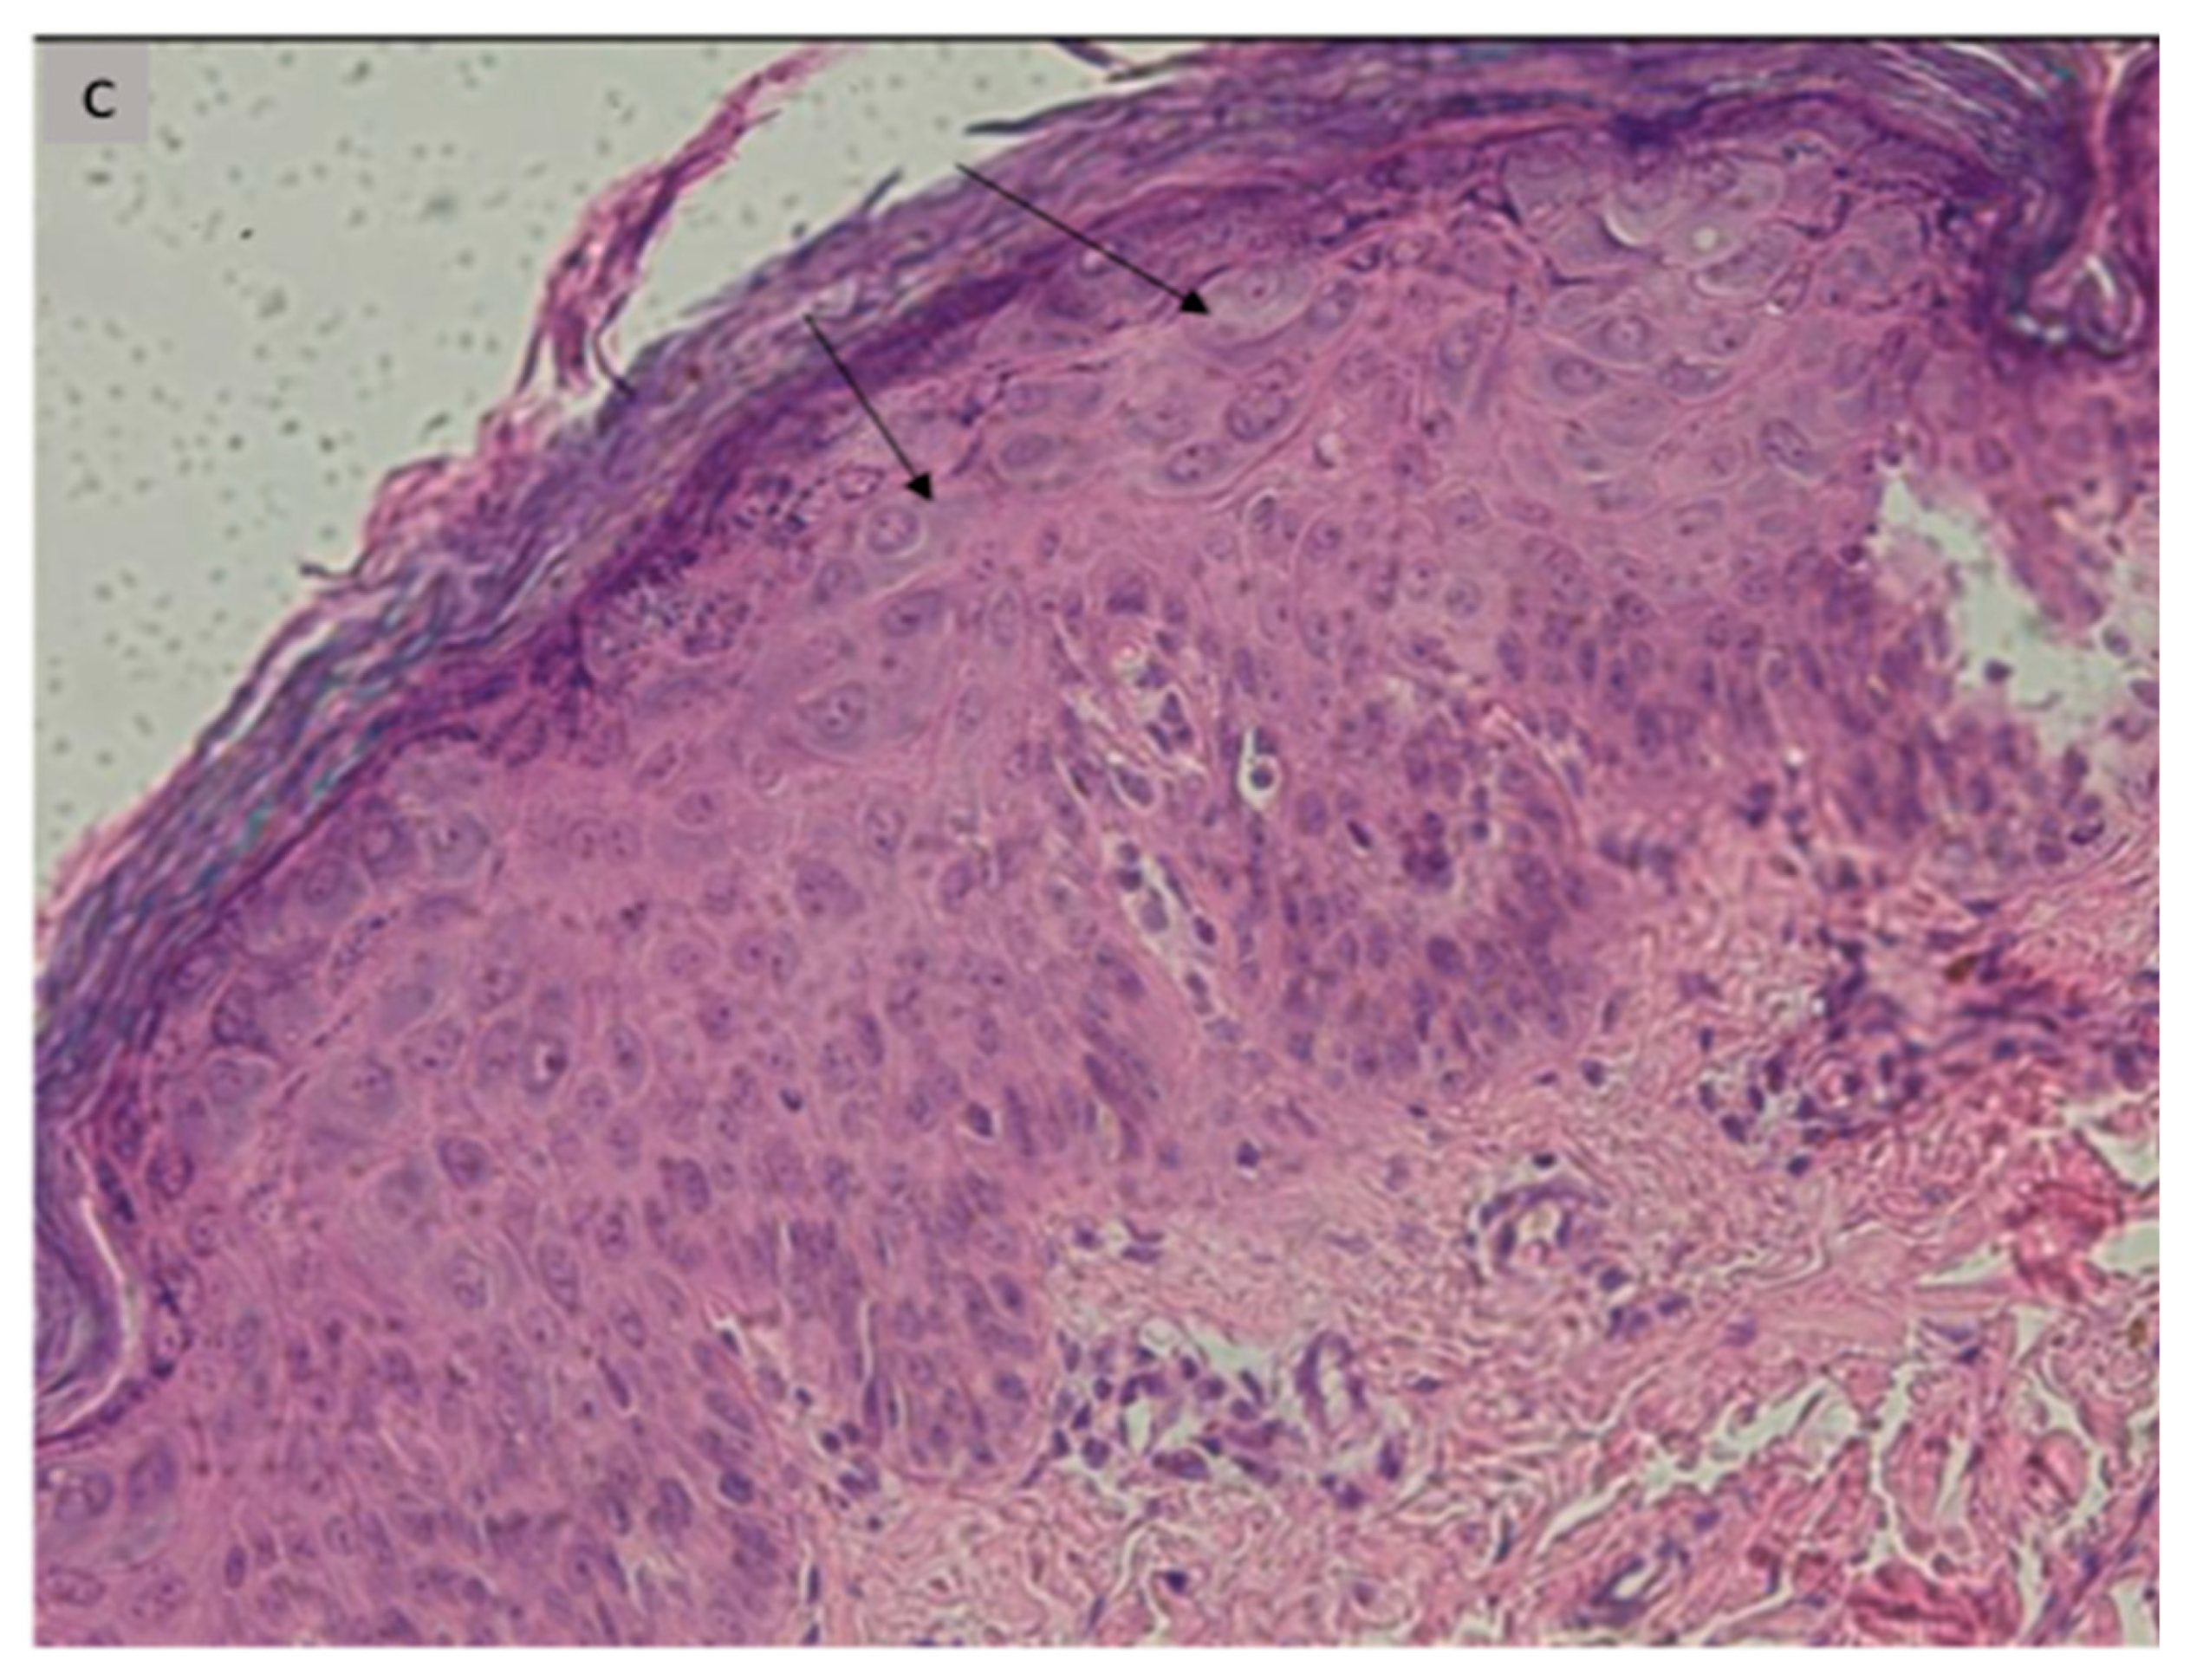

| 1 | 12 | M | Recalcitrant profuse verrucous lesions (flat and pityriasiform warts) since the age of 6 years | Face, neck, trunk, arms | Sister followed for CVID Recurrent diarrhea since the age of 10 | Lymphopenia 900/mm3 | CD3+: 771/mm3 CD4+: 253/mm3 CD19+: 128/mm3 CD16+, CD56+: 743/mm3 | Koilocytes, keratinocytes with pale blue cytoplasm in the upper epidermis associated with high levels of intranuclear viral replication | STK4 (homozygous, c.1305 + 1G > A) | LOCID+ Syndromic epidermo- dysplasia verruciformis |

| 6 | 8 | F | Profuse recalcitrant warty lesions (flat and pityriasiform warts) Since the age of 3 years | Face, neck trunk, arms, forearms, hands | Recurrent respiratory infections since the age of 3 years, with stature weight repercussions, Diarrhea | Neutropenia 580/mm3 Lymphopenia: 1750/mm3 | CD4+: 254/mm3 CD19+:130/mm3 CD16+, CD56+: 64/mm3 | Koilocytes, keratinocytes with pale blue cytoplasm in the upper epidermis associated with high levels of intranuclear viral replication | STK4 (homozygous, c.750G > A, p.W250) | CID+ Syndromic epidermo- dysplasia verruciformis |